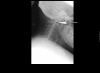

Background: The anaesthetic management of patients with Morquio syndrome is complicated by a number of factors including odontoid hypoplasia, atlantoaxial instability, thoracic kyphosis, and deposition of mucopolysaccharides in the soft tissue of the oropharnyx.